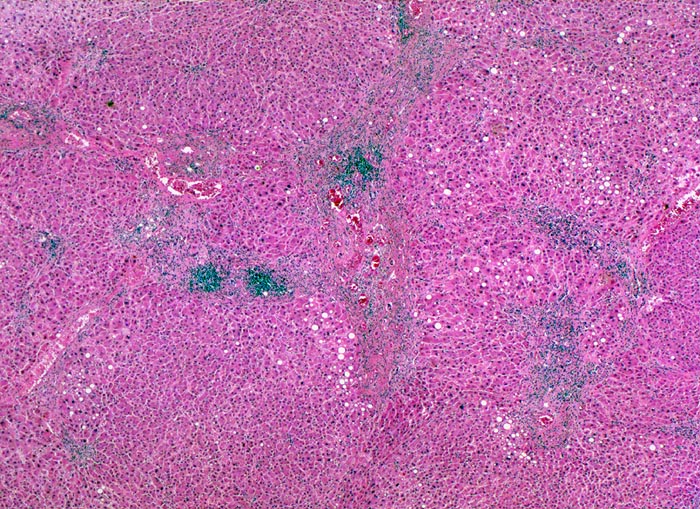

Morphologie: Makroskopisch imponiert das hepatozelluläre Karzinom als solitäre grosse Tumormasse, als zahlreiche zirrhoseartige Knoten oder als scharf begrenzter Knoten mit oder ohne Kapsel. Die tumorfreie Leber ist in der Mehrheit der Fälle zirrhotisch umgebaut. Mikroskopisch bilden die Tumorzellen mehr als 2 Zellen breite Trabekel ( 1237), kompakte Tumormassen ( 1229) oder pseudoglanduläre Strukturen (dilatierte Canaliculi) ( 1212)( 1199). Desmoplastisches Bindegewebe fehlt meist. Innerhalb des Tumors fehlen Portalfelder. Es finden sich lediglich Arterien. Etwa bei der Hälfte der Karzinome lässt sich intrazytoplasmatische oder intracanaliculäre Galle ( 1238) nachweisen. Immunhistochemisch lassen sich mit einem polyklonalen Antikörper gegen Carcinoembryonales Antigen (CEA) Gallecanaliculi zwischen den Tumorzellen nachweisen. Die Tumorzellen bilden keinen Schleim.

Therapie: Resektion oder orthotope Lebertransplantation (OLTx) bei ausgewählten Patienten werden in kurativer Absicht durchgeführt. Bei der Diagnosestellung ist bei den meisten Patienten das Tumorstadium oder die Leberinsuffizienz jedoch so weit fortgeschritten, daß eine Resektion oder eine Lebertransplantation nicht mehr möglich ist. In diesen Fällen kann eine lokale Therapie (Perkutane Ethanol-Injektion ( 1192)( 528), Radiofrequenz-Thermoablation, Transarterielle Chemoembolisation) eines kleinen Karzinoms durchgeführt werden.

Galle ist sichtbar in den Pseudodrüsen.

Tumorfreies Parenchym mit chronischer viraler Hepatitis (B und D): dichtes chronisches Entzündungsinfiltrat in den Portalfeldern übergreifend auf das Parenchym (Interfacehepatitis). Spärliche intralobuläre Entzündung mit Einzelzellnekrosen (Apoptosen). Fibrose der Portalfelder mit Septenbildung und unvollständigem zirrhotischem Umbau. Geringe gemischttropfige Verfettung des Leberparenchyms.